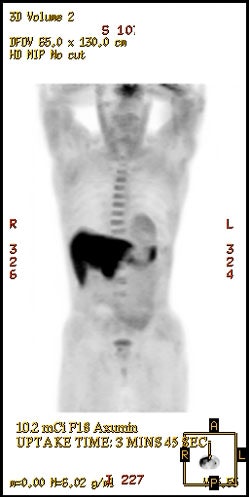

|

18F-Fluciclovine

biodistribution: The image below demonstrates

physiologic tracer activity. There is also a small focus

of abnormal uptake in the right aspect of the prostate.

Click image to view MIP cine. |